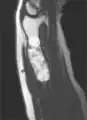

MRI showing enchondromas localized in the lower part of the radius of a 37-year-old patient affected with Ollier disease.

Enchondromas localized in the upper part of the humerus of the same patient